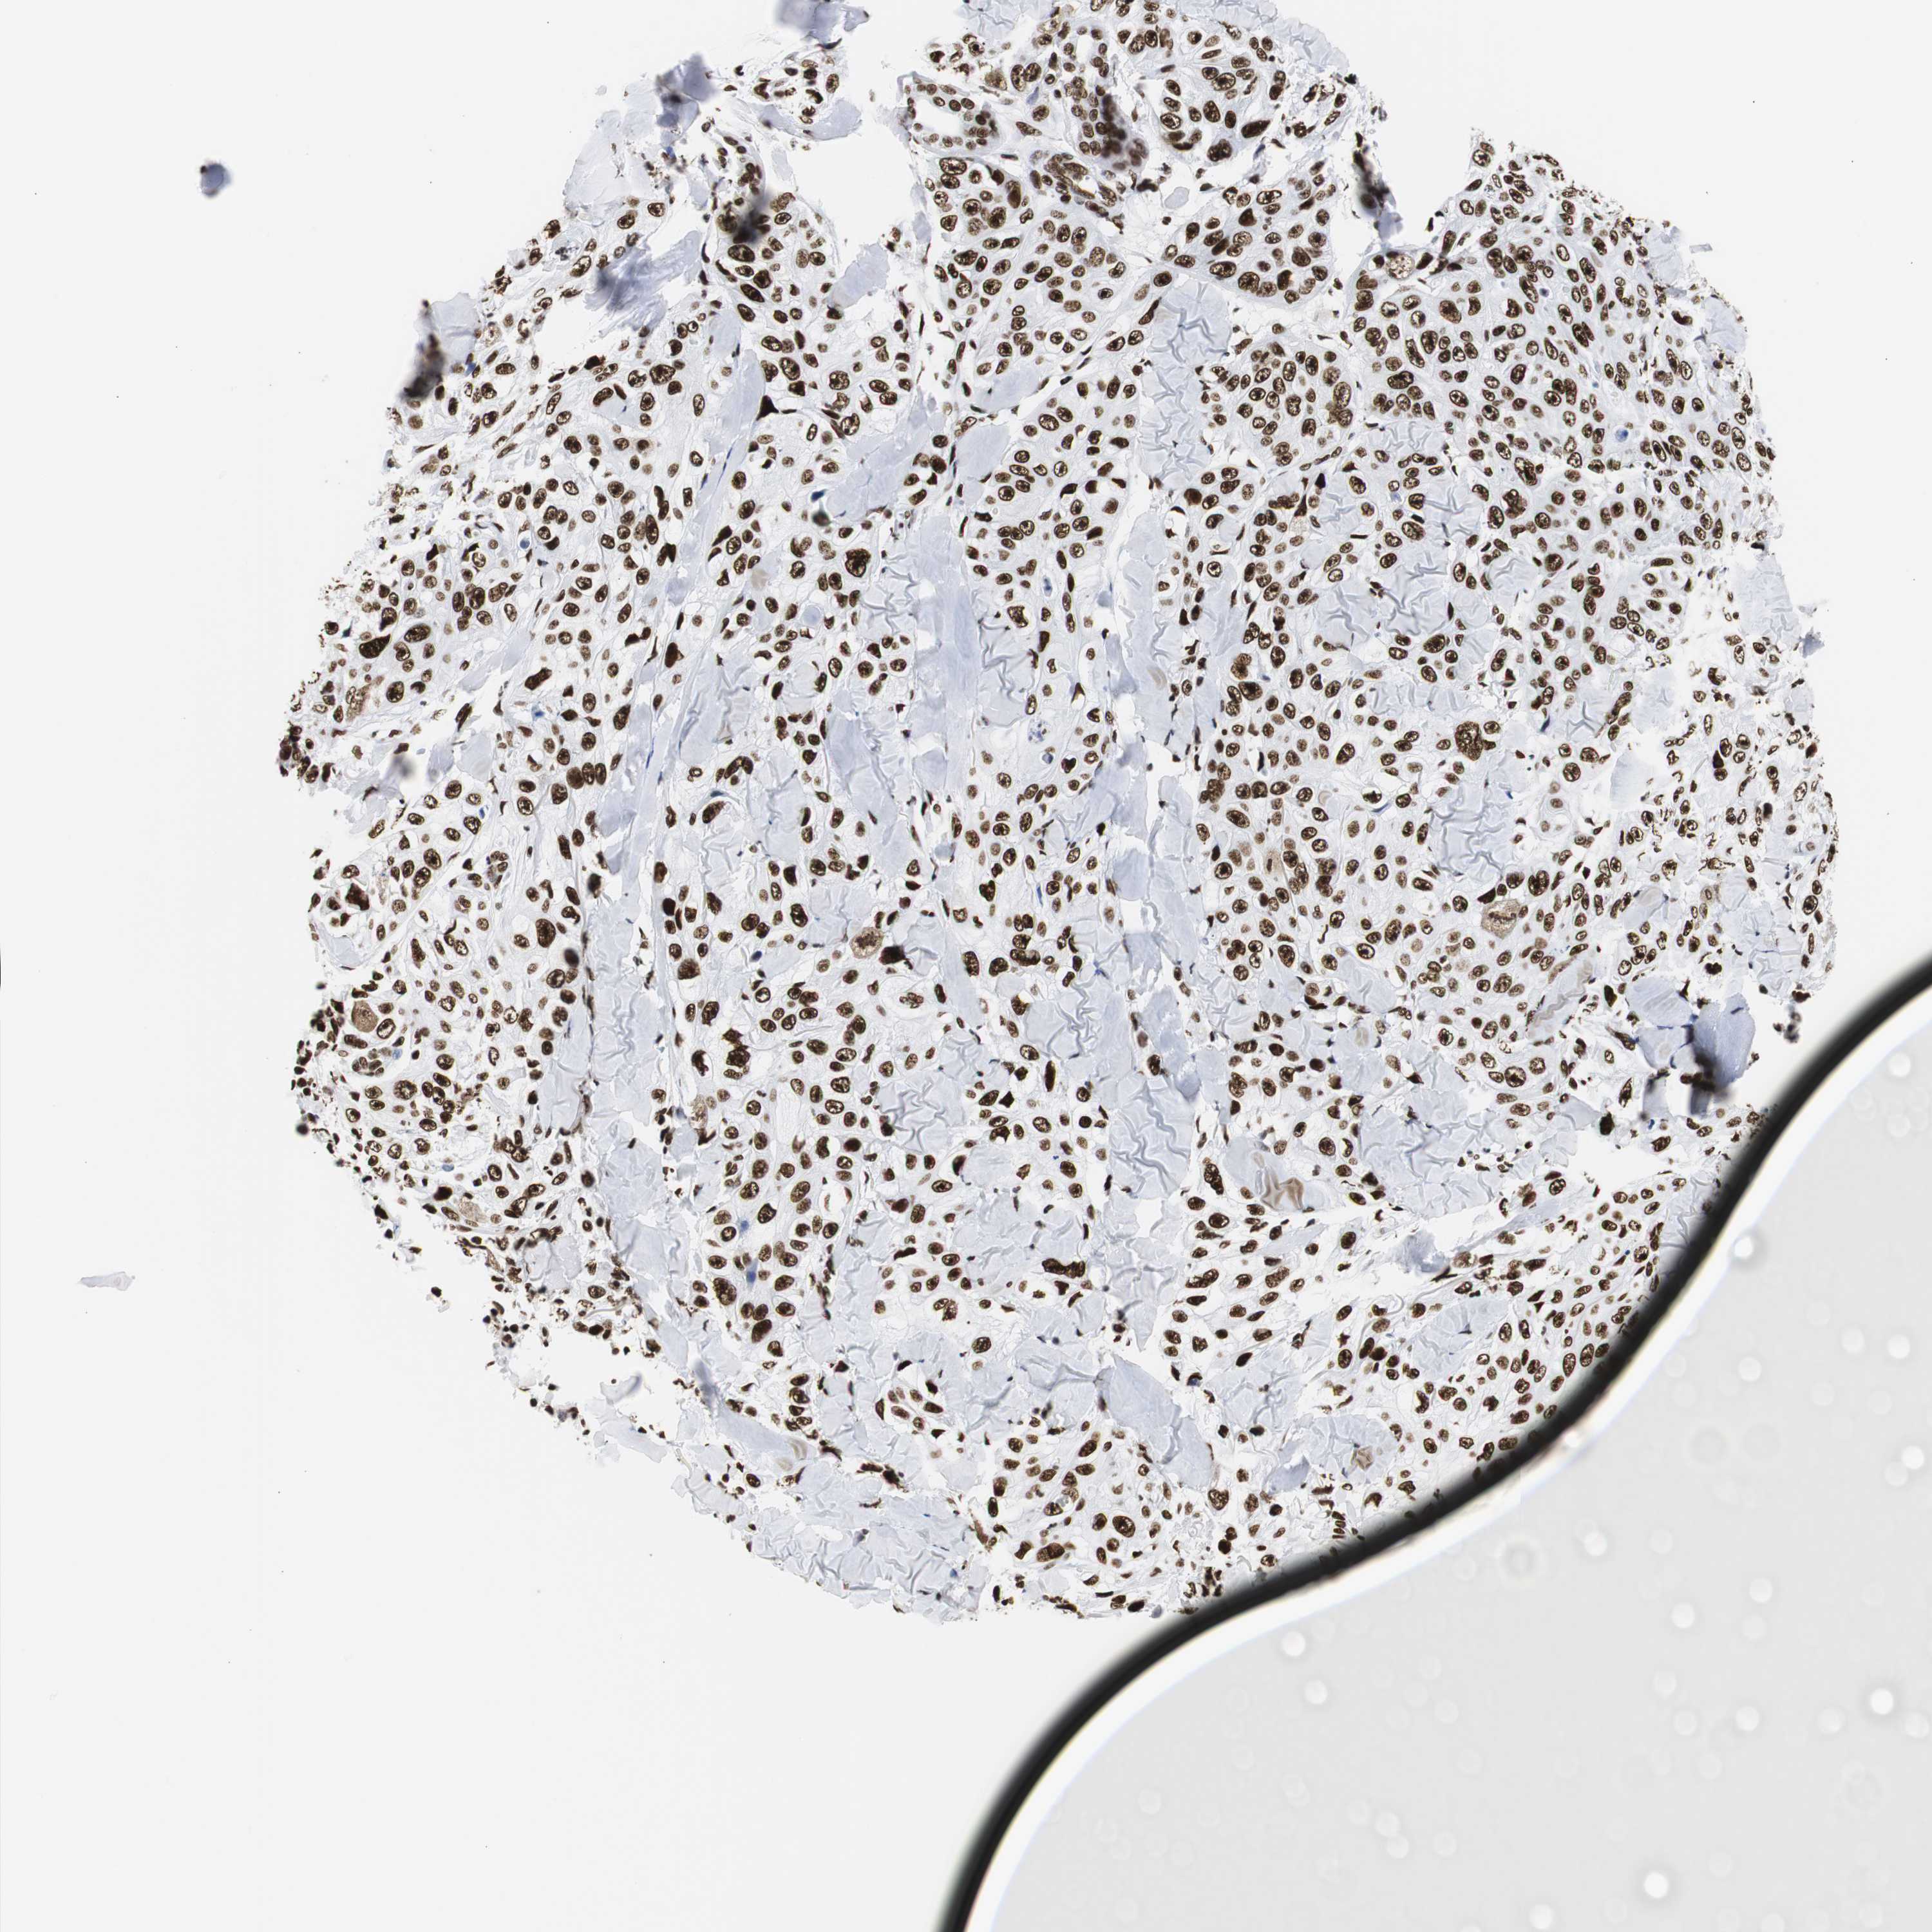

SKIN CANCER - Protein expressioni

A mouse-over function shows sample information and annotation data. Click on an image to view it in a full screen mode. Samples can be filtered based on level of antibody staining by selecting one or several of the following categories: high, medium, low and not detected. The assay and annotation is described here.

Each image is clickable and will lead to virtual microscopy that enables deeper exploration of all samples and also displays staining intensity scores, fraction scores and subcellular localization as well as patient and tissue information for each sample.

Antibody HPA001359

Staining

High

Strong

>75%

Location

Nuclear

Squamous cell carcinoma, NOS